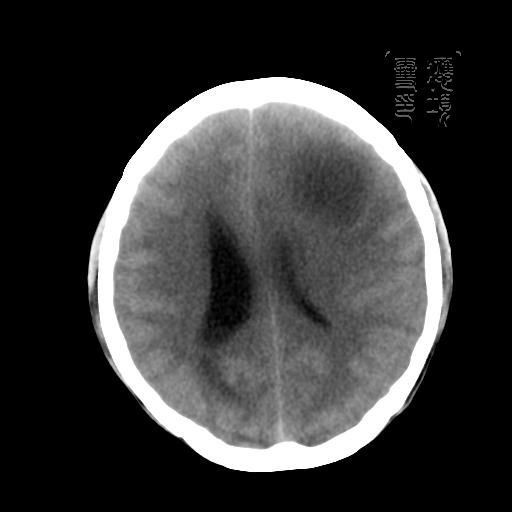

m 52y

二月前癫痫入院, 无既往史,现头痛、呕吐、视力减退、复视行ct平扫及增强检查。

见环形,结节样强化,考虑囊性星型细胞瘤。

考虑囊性星型细胞瘤,ct征象大囊小结节.

左额叶囊实性占位,以囊性为主,并见明显强化不规则壁结节,占位效应明显,首先考虑是囊性星形细胞瘤.